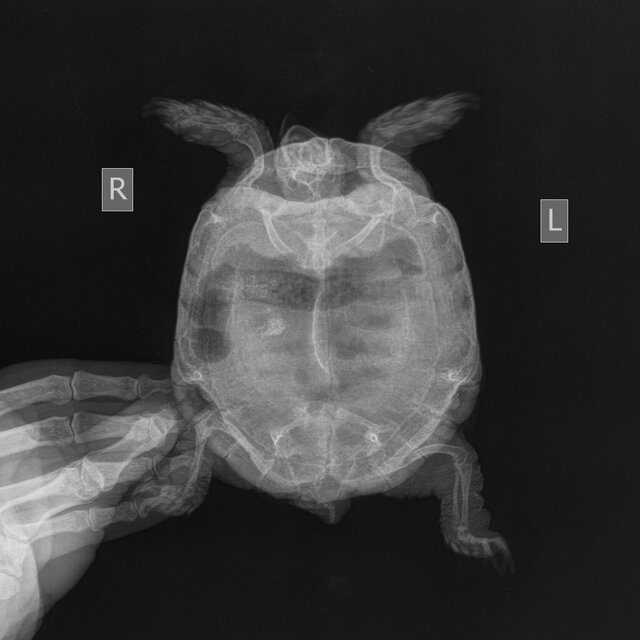

15.09.2023 были на приеме у герпетолога Борец М.Л. в клинике "Аист-Вет". Подрезали клюв и когти, сделали рентген. Врач сказал, что у черепахи сильный дефицит кальция, есть небольшое скопление каловых масс, но не критичное. Сделал следующие назначения: делать вибротерапию, купать каждый день организовать правильные условия жизни.